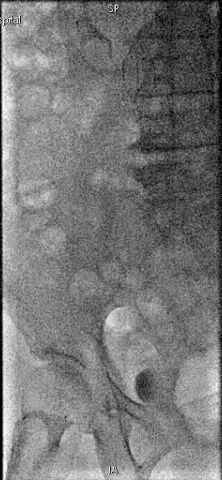

手术过程

抽吸结果